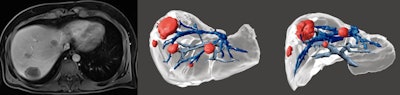

3D models that combine vascular and biliary anatomy using different imaging techniques can contribute to more rigorous planning of complex liver operations, including hepatic resections, living-donor transplantation, vascular intervention procedures, and biliary reconstruction surgery, Portuguese researchers reported at RSNA 2020.

3D models are increasingly used to help surgeons, guiding them through the complex hepatic vasculobiliary anatomy. They can help in the resection of hepatic primary tumors and metastasis because they can demonstrate the location within hepatic segments and the relationship with adjacent structures such as hepatic and portal veins, arteries, and bile ducts.

3D models are useful in surgical planning, and optimal resection planes can be selected prior to surgery. In patients at risk of post-hepatectomy liver failure, liver volumes may be calculated for various possible resection approaches.